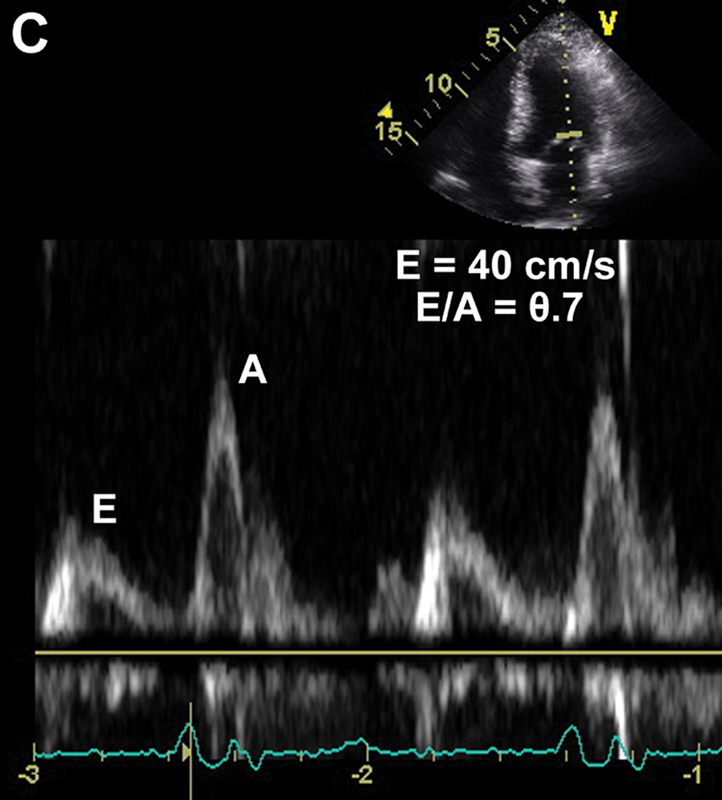

فحوصات تشخيصية لبعض امراض القلب والشرايين التاجية